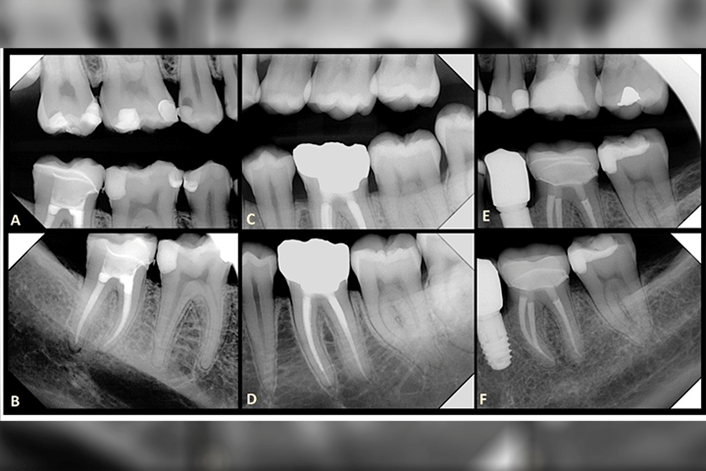

Now online in the Journal of Prosthodontics, a report of a randomized, double-blind, clinical trial that assessed the survival of endocrowns made from three different monolithic ceramic materials, and evaluated patient satisfaction.

Fifty-three patients (60 root canal treated molar teeth) were enrolled. Teeth were prepared to a flat butt-joint margin and randomly divided between three material groups: lithium disilicate-reinforced glass-ceramic, monolithic zirconia and polymer infiltrated hybrid ceramic. Clinical assessment using modified USPHS criteria was carried out after two years.

The overall Kaplan-Meier survival estimate among all groups was 90.9% with no statistically significant difference between the groups. Patient satisfaction ranged from 82.3% in the zirconia group to 100% in both the lithium disilicate and hybrid ceramic groups. Lithium disilicate-reinforced ceramic had fewer complications and required less intervention compared with zirconia and hybrid ceramics.

Endocrowns provide a predictable option for the restoration of endodontically treated molar teeth in the short term, however, long-term follow-up is required to substantiate these results.